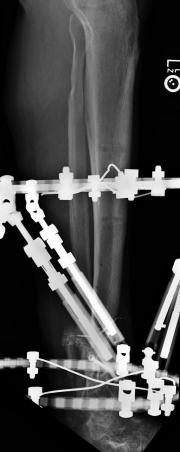

Post-corrective surgery X-Rays of the damaged right & left legs / ankles

The first two x-rays show Liam’s left ankle and pelvis prior to the accident. For comparison purposes it is interesting to see the

differences. The next x-rays were taken after the corrective surgery performed by Dr. Armendariz. Noticed that Dr. Armendariz has used tibia

bracing and also aligned the bone fragments of the left leg so that they could heal in the proper orientation. The external fixation has been

removed and Liam’s left foot has been returned to a more natural alignment.